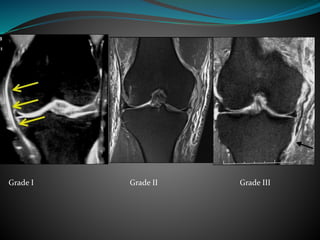

 Grade

Grade 1- Globular signal within the meniscus

Grade 2- Linear signal within the meniscus

not reaching the articular surface

Grade 3- Linear signal within the meniscus

reaching the articular surface

Grade I

Grade II

Grade III

Medial Collateral Ligament

 Grade I- Mild partial interstitial tear ,appears as edema

along superficial aspect

 Grade II- Extensive interstitial partial tear ,appears as

thickening of ligament with internal signal

abnormality or frank thining due to extensive partial

tear

 Grade III- Complete rupture of ligament

Grade I Grade II Grade III